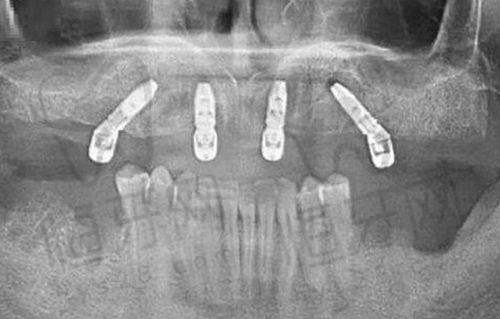

种植修复是门诊部的另一大特色项目。门诊部开展各类牙齿种植手术及修复治疗,能够根据患者的具体情况选择合适的种植体和修复方案。种植牙可以修复牙齿的咀嚼功能和美观度,让患者重新拥有健康的牙齿。

在种植修复领域,门诊部可能配备了精良的种植导航系统。种植导航系统可以通过计算机模拟种植过程,帮助医生更加精细地确定种植体的位置和方向,提高种植手术的成功几率和安心性。同时,精良的种植体材料也能够更好地与患者的口腔组织相融合,提高种植牙的使用寿命和稳定性。